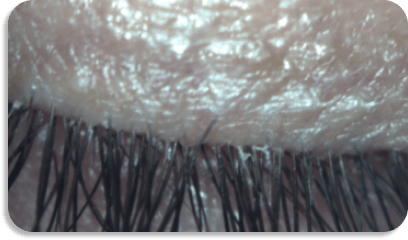

Before XDEMVY